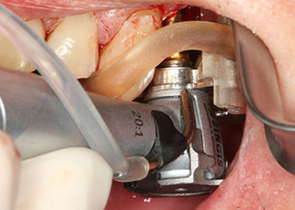

新一代口腔种植导板

西泰克双导(TwinGuide)数字化种植辅助系统,利用自研的TG-System系统、TG-Design设计软件、结合TG-Ai系统和设计团队为牙医提供安全可靠的种植方案,并通过3D打印生成产品。

双引导更精准

术野更开阔

冷却更充分

西泰克双导(TwinGuide)数字化种植辅助系统,利用自研的TG-System系统、TG-Design设计软件、结合TG-Ai系统和设计团队为牙医提供安全可靠的种植方案,并通过3D打印生成产品。